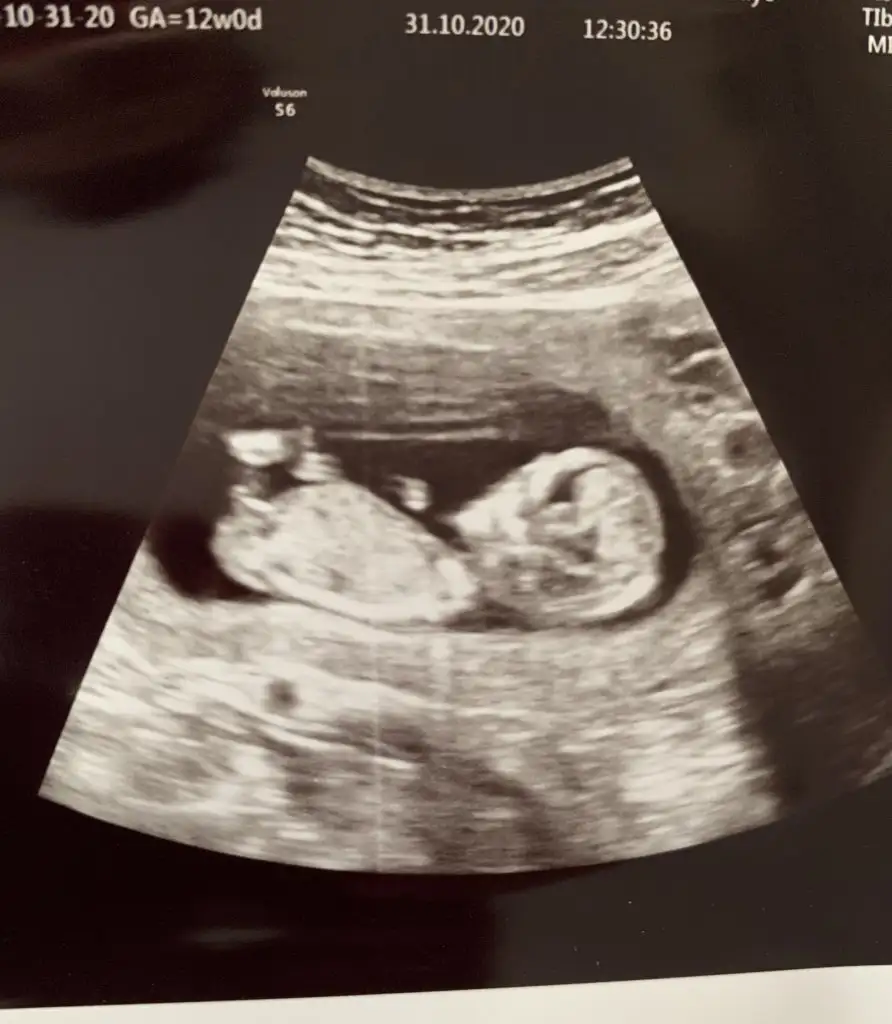

Bana da bakabilir misiniz 12+2

Eklentiler

• 03C91A9F-DC60-42B4-83D6-B415BB44D01A.webp

42,9 KB · Görüntüleme: 139